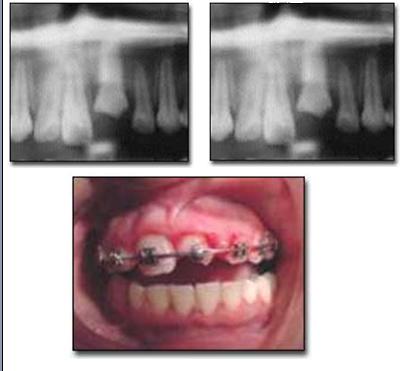

Intrusión con fractura coronaria

Caso clínico de intrusión con fractura en diente tratado endodónticamente, el diente contiguo se perdió por avulsión. El diente intruído fue traccionado ortodóncicamente con arcos de níquel titanio.